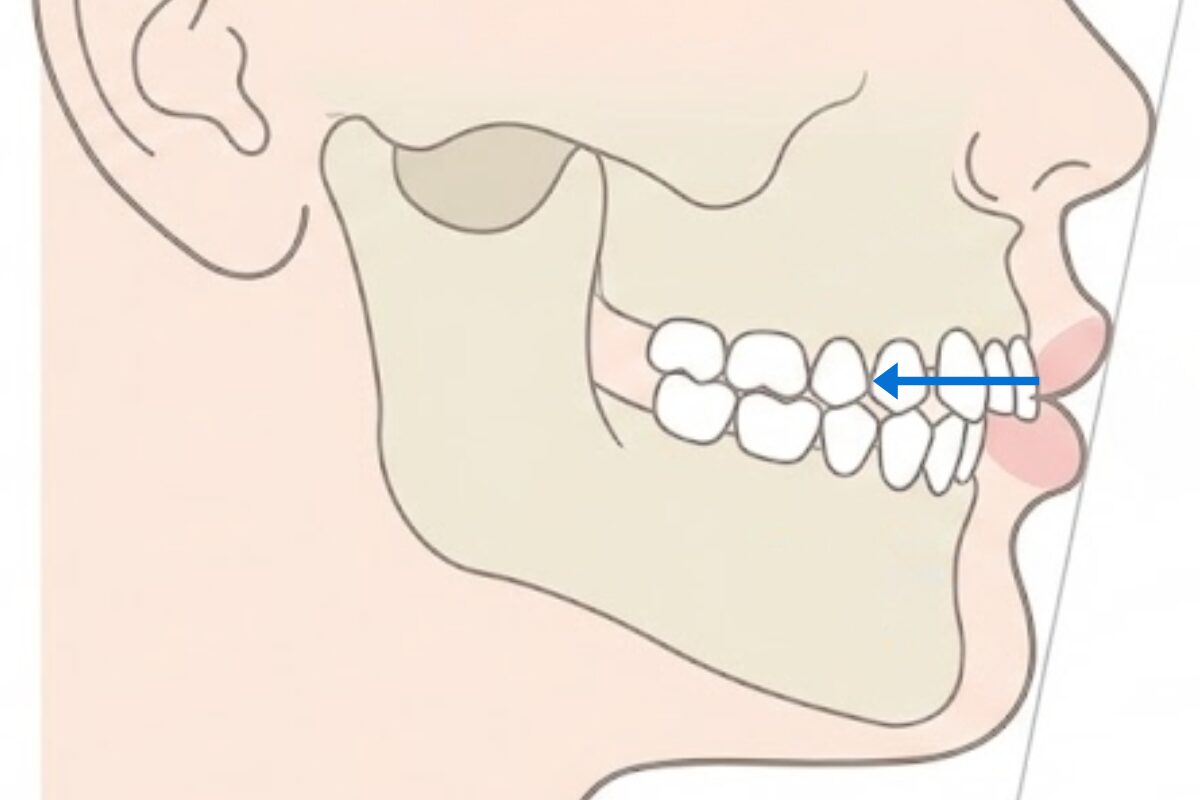

原因は、骨格を考慮せずに歯だけを下げてしまうこと。

出っ歯には歯の傾きだけでなく骨格が関係しているケースも多く、

歯だけを見て下げると、適切な下げ幅を見誤りやすいのです。

出っ歯の見え方は、前歯の傾きだけでなく、あごの前後位置(骨格)も関係しています。

歯の角度だけを見て治療を進めると、「下がったけど口元が貧相になった」といったギャップが生まれやすくなります。

そのため当院では、歯と骨格の両面から”ベストな下げ幅”を見極める診断を行っています。